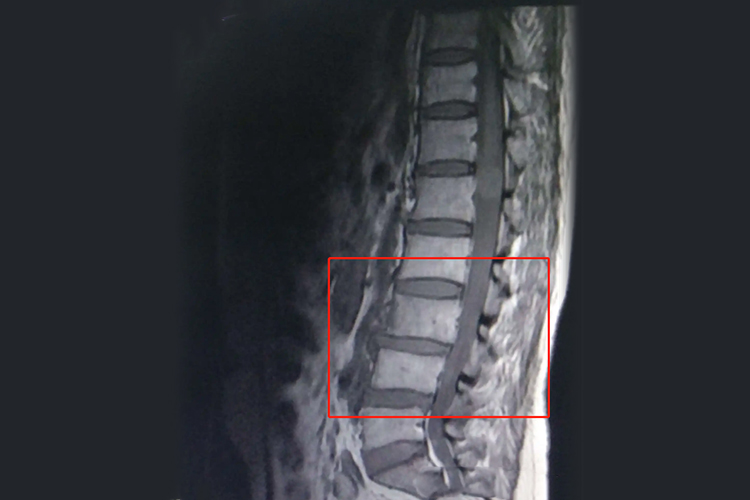

3、MRI检查

- 以其无辐射、多参数成像及软组织分辨率高等特点,在腰间盘病变的诊断中具有重要意义。MRI检查能够清晰地显示椎间盘的形态、结构及其与周围组织的关系,包括椎间盘的髓核突出、纤维环破裂等细节。

- MRI还能通过不同层面的矢状像及轴位像观察病变椎间盘的具体位置和占位情况,为临床治疗方案的制定提供有力依据。